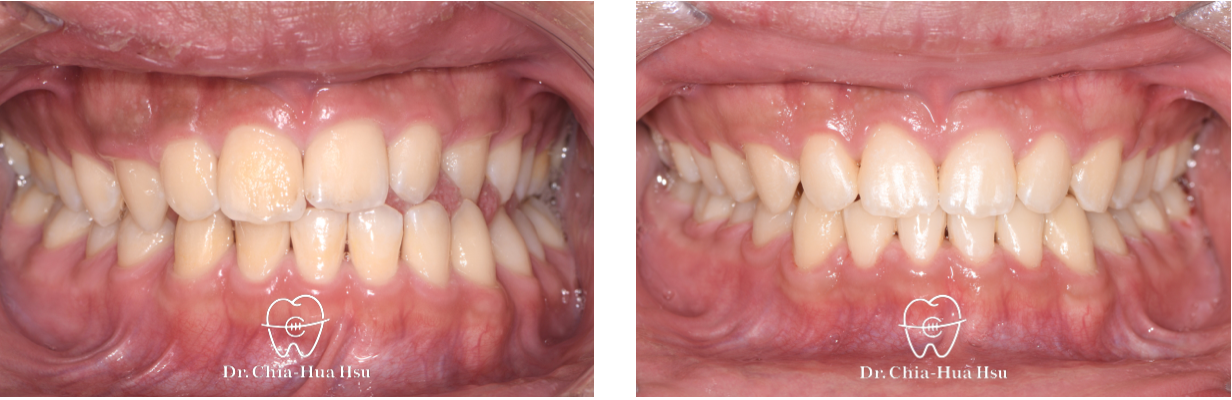

• 治療過程:治療過程使用『陰陽線』,來改善咬合平面歪斜的問題。

• 矯正小知識:『陰陽線』是利用特殊設計的 Beta-titanium arch wire (TMA) 線材(一條往上一條往下,像是太極的陰陽)來調整上顎咬合面的傾斜,改善患者的咬合面傾斜問題,並避免手術的痛苦。

治療前

治療後